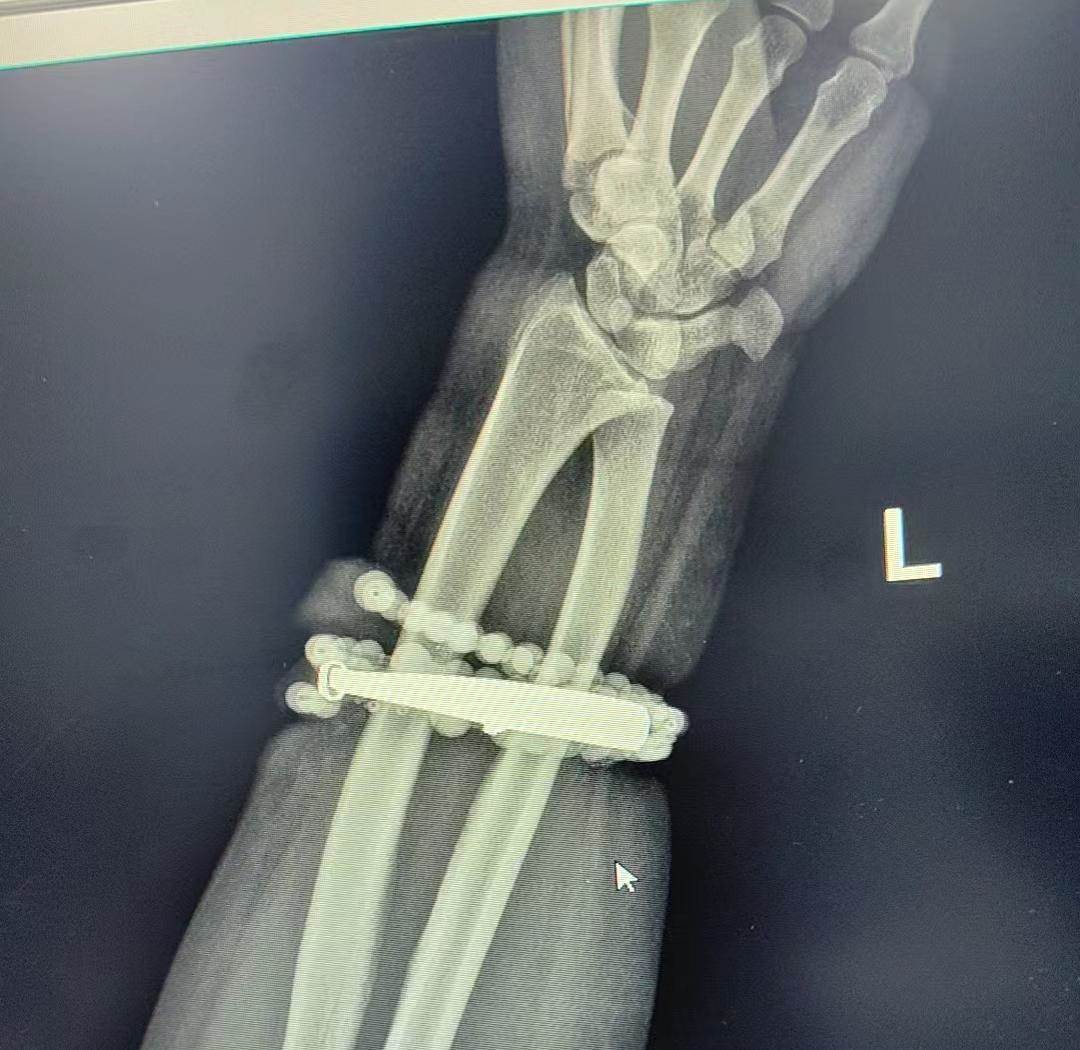

」 龔女士到了寧德市閩東醫院,掛了創傷骨科的號,接診的黃其龍副主任醫師一看到她的手腕,臉色就嚴肅起來:「這是典型的長期壓迫導致的慢性炎癥,還引發了肉芽組織增生,手鐲和串珠已經成了‘病灶’,必須馬上手術取出來,不然感染擴散到骨頭,手臂功能都可能受影響。」

進一步檢查后,醫生發現龔女士的情況比想象中更嚴重:銀手鐲的邊緣已經深深嵌進皮下組織,周圍的皮膚因為長期摩擦和壓迫,形成了厚厚的肉芽增生,還伴隨嚴重細菌感染,要是再拖下去,感染可能蔓延到前臂的肌肉和骨骼,到時候不僅要截肢,甚至可能引發敗血癥危及生命。